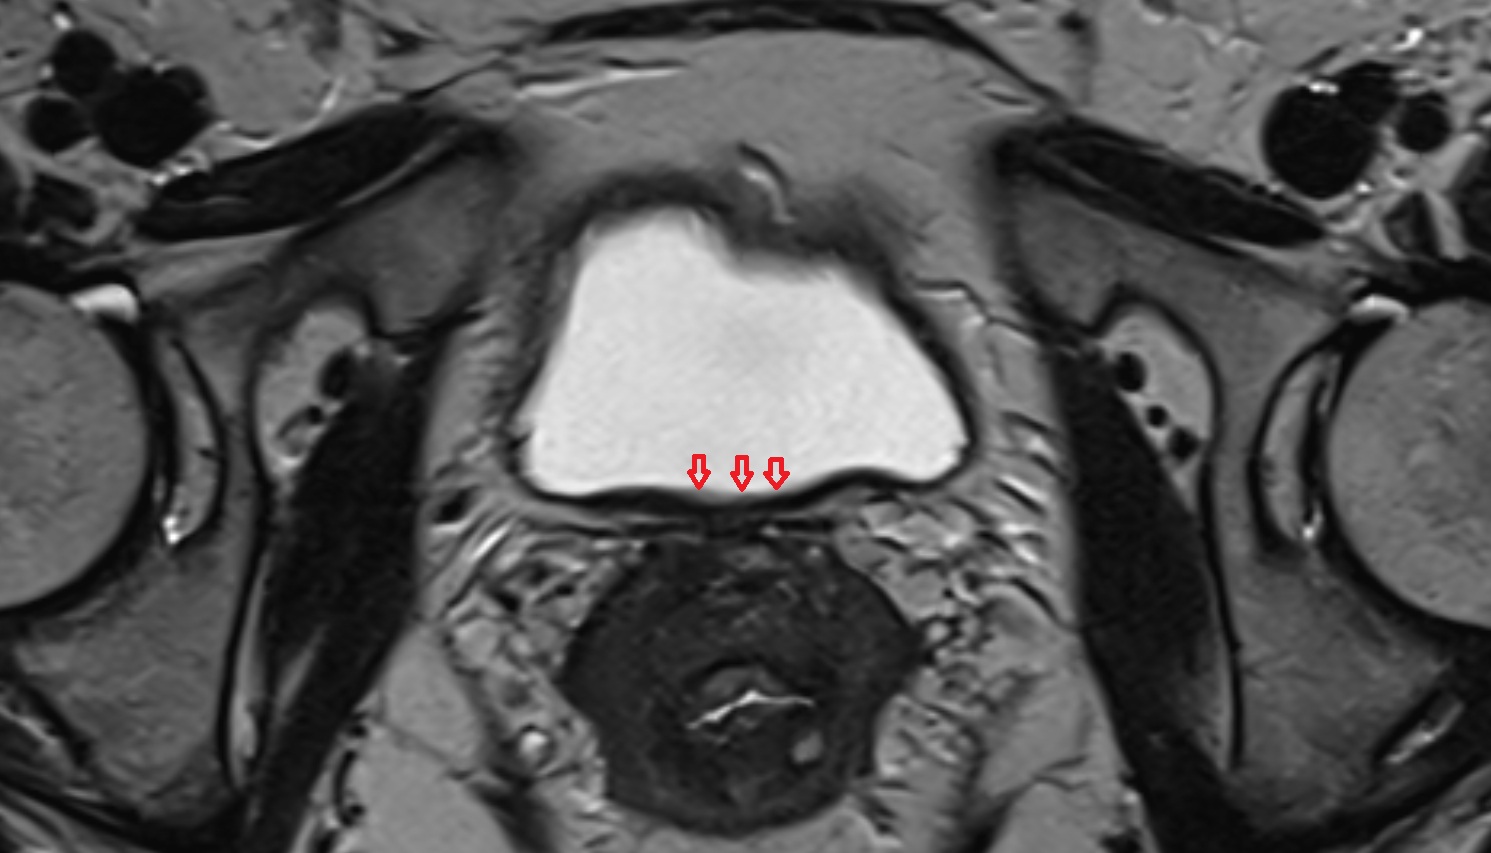

- Peripheral zone of prostate

- Anterior Fibromuscular Stroma of prostate

- Central zone of prostate

- Transitional zone of prostate